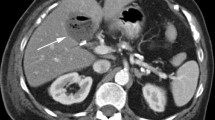

38-year-old female patient with history of cholecystectomy which was complicated by bile duct injury. a Axial T1-weighted MR precontrast image of bile duct injury. b Axial T1-weighted MRI (20 min after administration of Gd-EOB-DTPA) shows excreted contrast within the intrahepatic ducts and with hyperintensity in the non-dependent portion of the perihepatic fluid (arrow). c More delayed images, obtained with 35-min delay, demonstrate expanding extraluminal contrast (arrow) within the perihepatic fluid confirming active bile leak. Patients were found to have Strasberg-type E1 injury (injury to extrahepatic bile duct > 2 cm distal to confluence) following attempted cholecystectomy